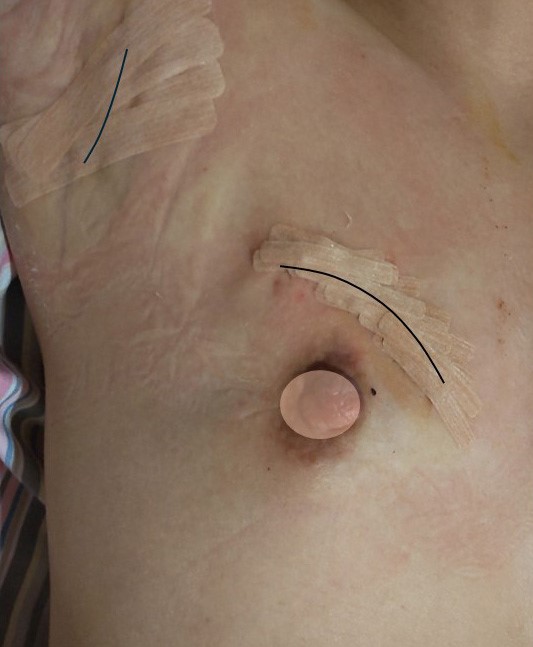

9. 実際の症例の傷

術後1日